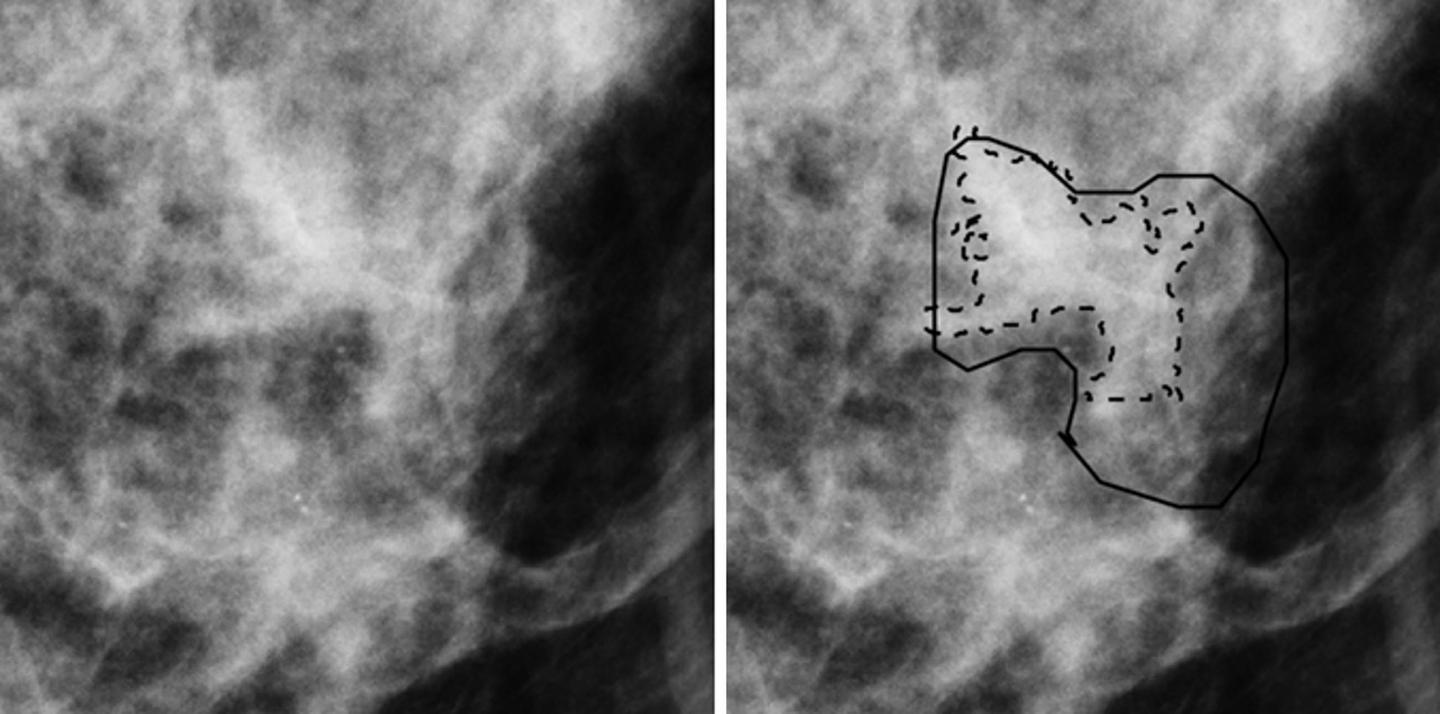

Region of interest from digital mammography depicts invasive cancer misclassified with mammography radiomics. Images in 50-year-old woman with invasive cancer (Breast Im¬aging Reporting and Data System category 4, with category C breast density) without (left) and with (right) radiologist and computer delineations (solid and dashed lines, respectively).